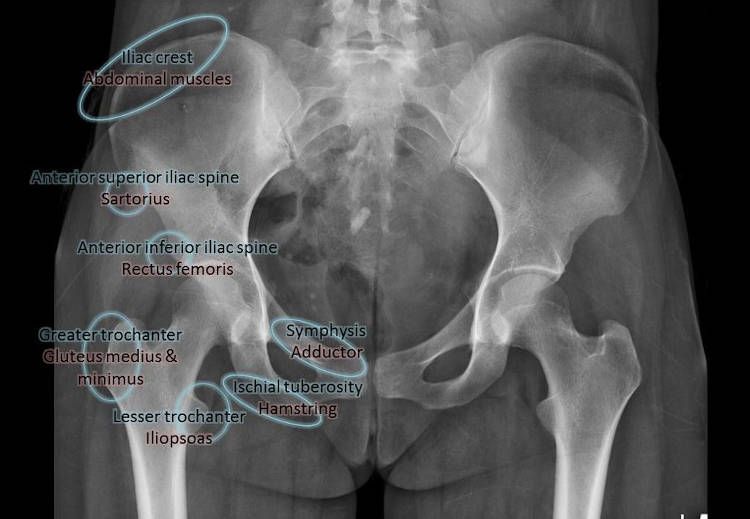

Στην περιοχή της λεκάνης συμπτωματολογία από υψηλή μυική φόρτιση εμφανίζεται περίπου στο 16ο -17ο έτος και αφορά συνήθως την πρόσθια άνω λαγόνια άκανθα – έκφυση του ραπτικού μυός, την πρόσθια κάτω λαγόνια άκανθα – ορθός μηριαίος και το ισχιακό όγκωμα (με συχνές αποσπάσεις στους ταχυδυναμικούς αθλητές) – οπίσθιοι μηριαίοι. Σημεία υψηλής μυικής τάσης και εμφάνισης άλγους εντοπίζονται επίσης: στον ελάσσονα τροχαντήρα – κατάφυση λαγονοψοίτη, στον μείζονα τροχαντήρα –στροφείς ισχίου και μέσος γλουτιαίος, λαγόνια ακρολοφία – κοιλιακοί, άνω γωνία ηβικής σύμφυσης – ορθός κοιλιακός. Η πολύπλοκη ανατομική της περιοχής της λεκάνης εγείρει διαγνωστικές αμφιβολίες πολλές φορές δυσεπίλυτες με τις απεικονιστικές προσεγγίσεις ανεπαρκείς (οστικά οιδήματα στις MRI, οιδήματα μαλακών μορίων στους υπερηχολογικούς ελέγχους).